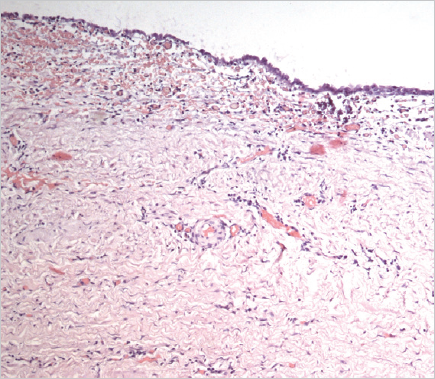

Histological examination of the removed paraurethral cyst was performed (Fig. 6–8).

Fig. 8.The wall of the paraurethral cyst, surgical material. Hematoxylin-eosin staining, ×100. Foci of epithelial lining atrophy are determined

Рис. 8.Стенка парауретральной кисты, операционный материал. Окраска гематоксилином и эозином, ×100. Определяются очаги атрофии эпителиальной выстилки